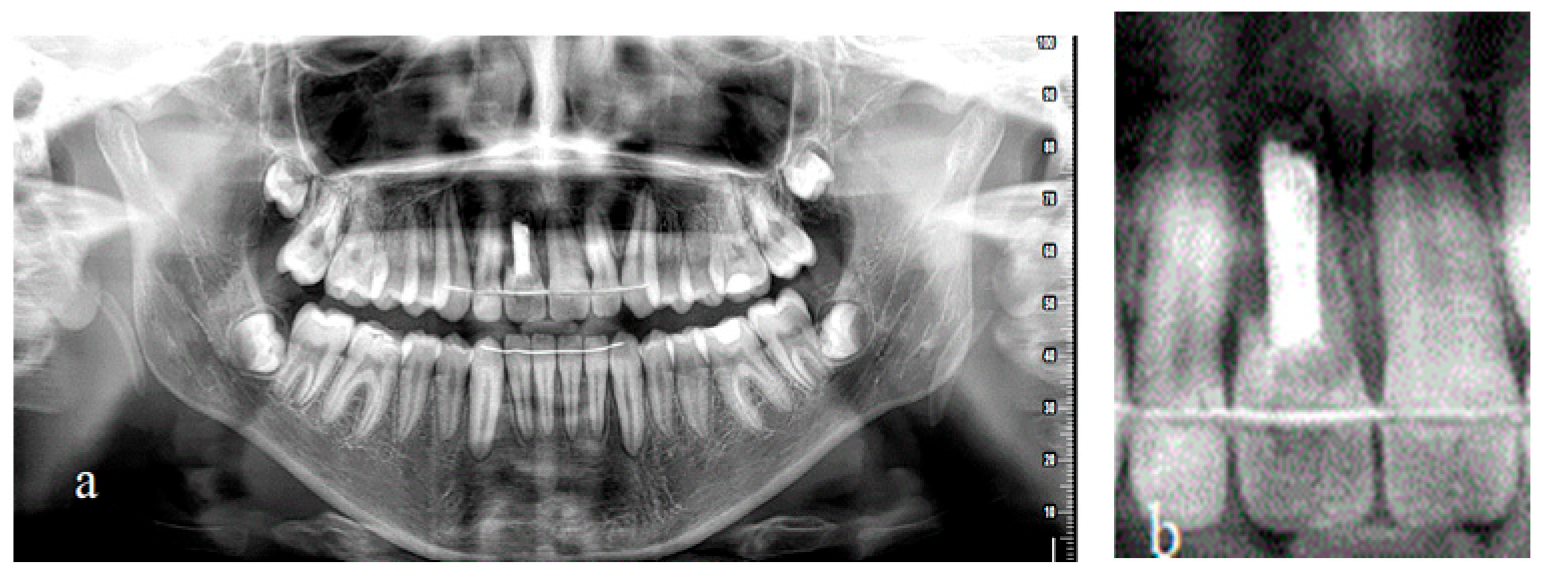

2. Materials and Methods